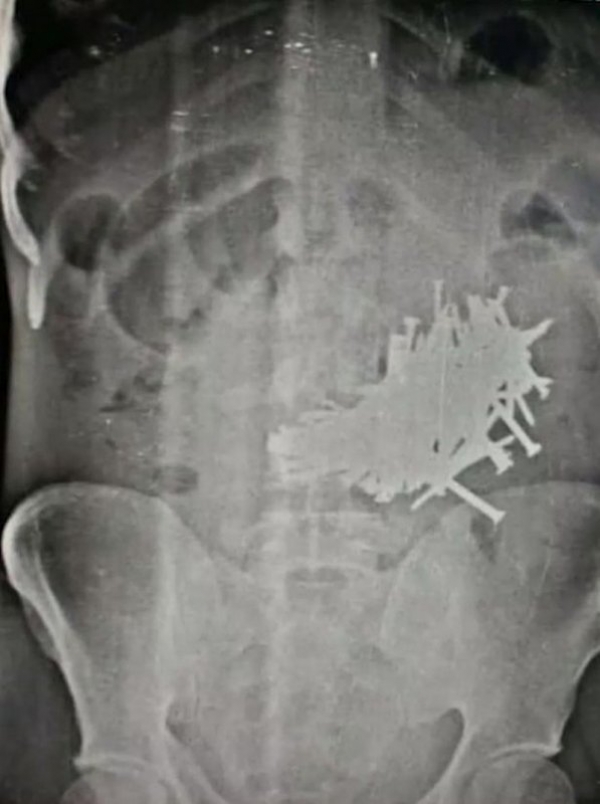

В больницу индийского штата Раджастхан доставили 43-летнего Бхола Шанкар, страдающего от сильных болей в животе. Оно и не удивительно — рентген показал наличие в его кишечнике огромного количества гвоздей. Во время операции хирурги вытащили из него 116 гвоздей (каждый длиной более 5 см). Бхола считал свое патологическое пристрастие глотать гвозди шизофренией, а потому до последнего скрывал свои гастрономические предпочтения от семьи.